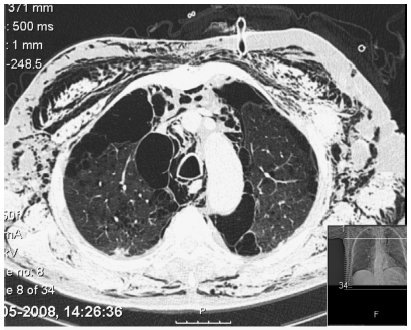

Ao 9.º dia de internamento verificouse novo agravamento clínico, com aumento da dispneia em repouso, dessaturação significativa e aumento marcado do enfisema subcutâneo. A telerradiografia torácica mostrou manutenção da câmara de pneumotórax apical à esquerda. Foi colocado novo dreno torácico (Joly n.º 18) no segundo espaço intercostal esquerdo, na linha axilar anterior (Fig. 2). Ambos os drenos ficaram funcionantes, a borbulhar com os movimentos respiratórios, tendo sido conectados a aspiração de baixa pressão. Por não melhoria clínica, com persistência de enfisema subcutâneo maciço (enfisema da face condicionando encerramento palpebral bilateral, do pescoço, do tórax e de ambos os membros superiores) e voz nasalada, foi efectuada TC torácica (Fig. 3), que mostrou enfisema subcutâneo extenso, pneumopericárdio e pneumomediastino, pneumotórax à esquerda de grau moderado, enfisema parasseptal e centrilobular difuso com bolhas apicais de grandes dimensões. Perante estes dados, foi solicitada a avaliação por Cirurgia Cardiotorácica que, dada a gravidade da DPOC, considerou que o doente não reunia as condições necessárias para ser submetido a tratamento cirúrgico.

Fig. 3 Corte de TC torácica